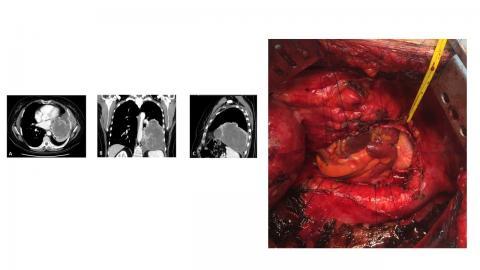

Chest wall resection and reconstruction

ECMO for pulmonary/mediastinal resections